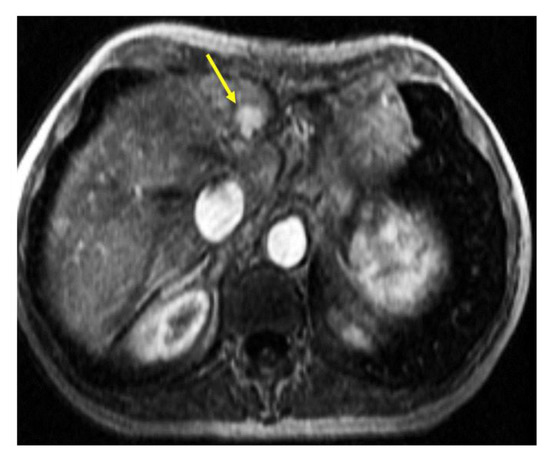

2. Case Presentation